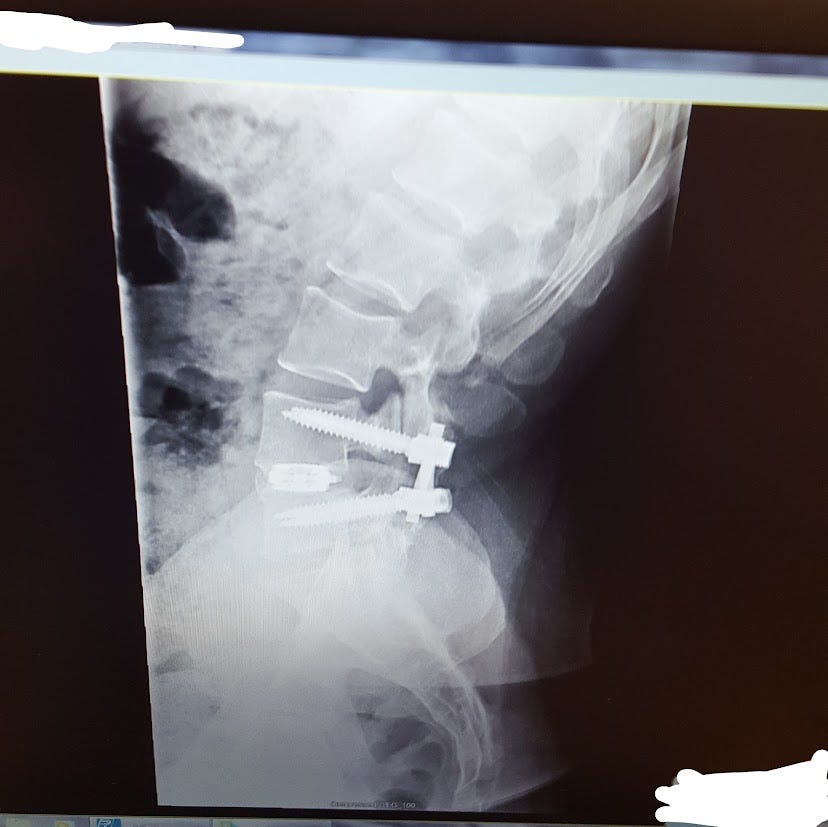

He eventually gave me the name of a spine specialist he trusted. I went to this surgeon. He looked at my MRIs, CAT scan, and X-Rays He pointed out where the Pars was, how it caused the rest of my pelvis and spine to rotate incorrectly (spondylolisthesis). He also showed a bulge, or tear, in my L5 S1. He wanted the list of injuries and surgeries.

I had them written down this time. He looked at the list and shook his head; after a moment, he asked if I was in a safe place. I didn’t understand the question. He said he could operate and fix it by fusing and decompressing the L4 and L5. I didn’t know what this meant; I knew of people who had back surgeries and got better soon after.